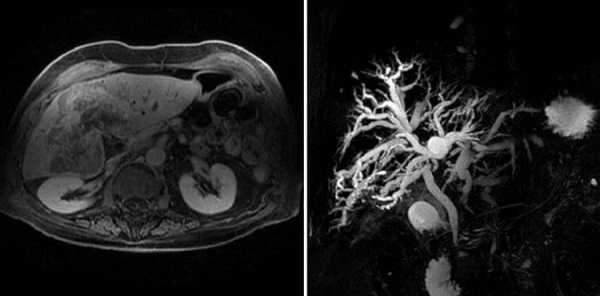

- MPT-холангиография. Точность данного метода исследования составляет до 97%. При выполнении МРТ- холангиографии получают изображение желчного пузыря и пузырного протока, сегментарных, долевых желчных протоков, общего печеночного протока, холедоха и панкреатического протока. Появляется возможность точной визуализации камней в просвете протоков, их сужения или расширения. К большим преимуществам МРТ-холангиографии относится ее неинвазивность и отсутствие необходимости в использовании контрастных веществ.

МРТ холангиография что показывает

Томограмма желчевыводящих протоков

МРТ холангиография позволяет оценить состояние желчного пузыря и протоков без использования инвазивных мер. Исключением является сканирование с контрастным усилением, когда пациенту внутривенно вводят препарат на основе растворимых солей (хелатов) гадолиния. Вещество отличается низкой токсичностью, гипоаллергенностью и выводится из организма естественным путем.

Опухоль Клацкина на снимках МР-холангиографии

Холангиокарцинома на снимках МРТ

Метод отличается высокой информативностью. Томограммы визуализируют состояние печеночного, пузырного, панкреатического протоков, отражают состояние окружающих тканей и кровеносных сосудов. Преимуществом МР-холангиографии является безопасность и отсутствие ионизирующей лучевой нагрузки.